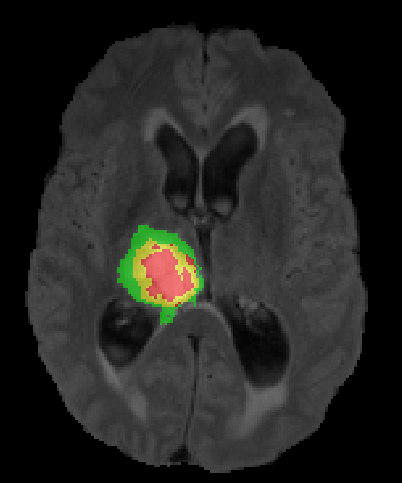

(a) Input images (b) Semantic Labels (c) Seg-Net+EG-CNN (d) Seg-Net

Geirhos et al. [35] empirically demonstrated that common CNN architectures are biased towards recognizing textures in the image, not object shape representations. This is in contrast to how humans normally segment images. In medical imaging for instance, expert manual segmentation often relies on the boundaries of anatomical structures; for example, to manually segment a liver, a medical practitioner usually identifies intensity edges first and subsequently fills the interior region in the segmentation mask. CNNs, which predominantly learn texture abstractions, often yield imprecise boundary delineations. Thus, CNN predictions often need to be post-processed to compensate for the shape details that the model fails to learn during training.

We argue that the sub-optimal paradigm of processing different abstractions within a single CNN pipeline can be remedied through the effective processing of information in a structured manner. Consequently, we devise strategies for disentangling the edge and texture information within a single training pipeline. Figure 2 illustrates how our proposed module, dubbed EG-CNN, can be paired with any existing CNN encoder-decoder to improve segmentation quality near intensity edges. We have applied our EG-CNN to the tasks of brain and liver tumor segmentation in medical images (Figure 3).

(1) Brain MR (2) Liver MR (3) Liver CT (4) Lung CT